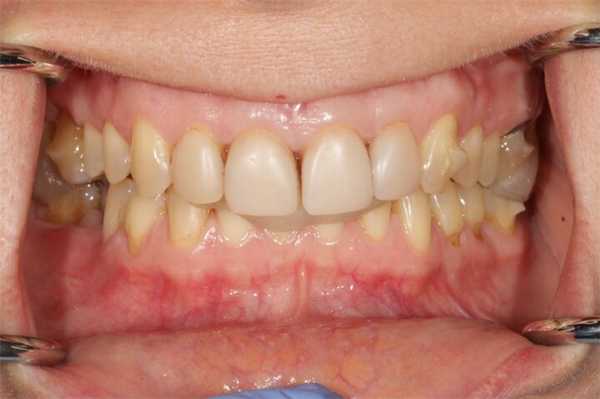

Пациентка К.,возраст 50 лет, обратилась к нам в клинику с жалобами на беспокойства в области височно нижнечелюстного сустава (щелчки, хруст, боль). Эстетическая неудовлетворенность видом своей улыбки, отсутствие зуба нижней челюсти справа. Это мешало полноценно пережевывать пищу на правой стороне.

На представленном ниже фото обратите внимание, что при сомкнутых зубных рядах зубы верхней челюсти очень сильно перекрывают зубы нижней челюсти (глубокое перекрытие), что увеличивает нагрузку на височно нижнечелюстной сустав, видим неровный зубной ряд.

- глубокое перекрытие центральными резцами нижних центральных резцов (глубокое перекрытие).

- глубокое перекрытие верхними зубами нижних,